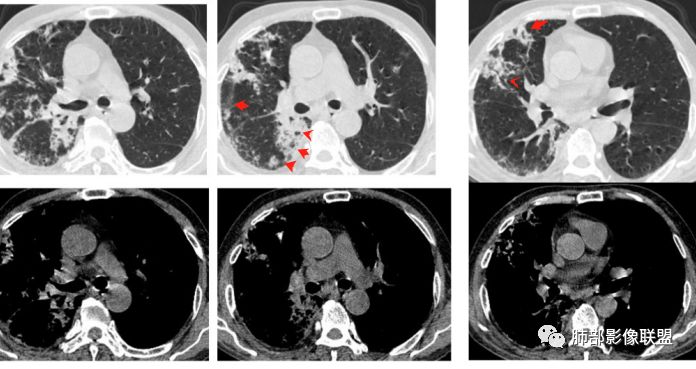

3.右肺巨大空洞影。值得注意的是:

1)空洞内坏死相对彻底(未见絮状物或丝状物等)。 医学百科网 | YxBaike.Com

2)空洞壁密实,内外壁都清楚,这是慢性病灶特征之一。 医学百科网 | YxBaike.Com

3)内壁不规则,多呈不规则山脊样突入,这些“脊”等同于空洞壁的密实。尽管洞腔内蜿蜒不规则,但并未形成洞壁的膨隆样结节影,换句话说,外壁看不出分叶!

这种空洞更多见于结核!

医学百科网 | YxBaike.Com

4)空洞病灶内显示液平。提示伴有细菌感染等。 医学百科网 | YxBaike.Com

5)肺门纵隔未见肿大淋巴结。 医学百科网 | YxBaike.Com